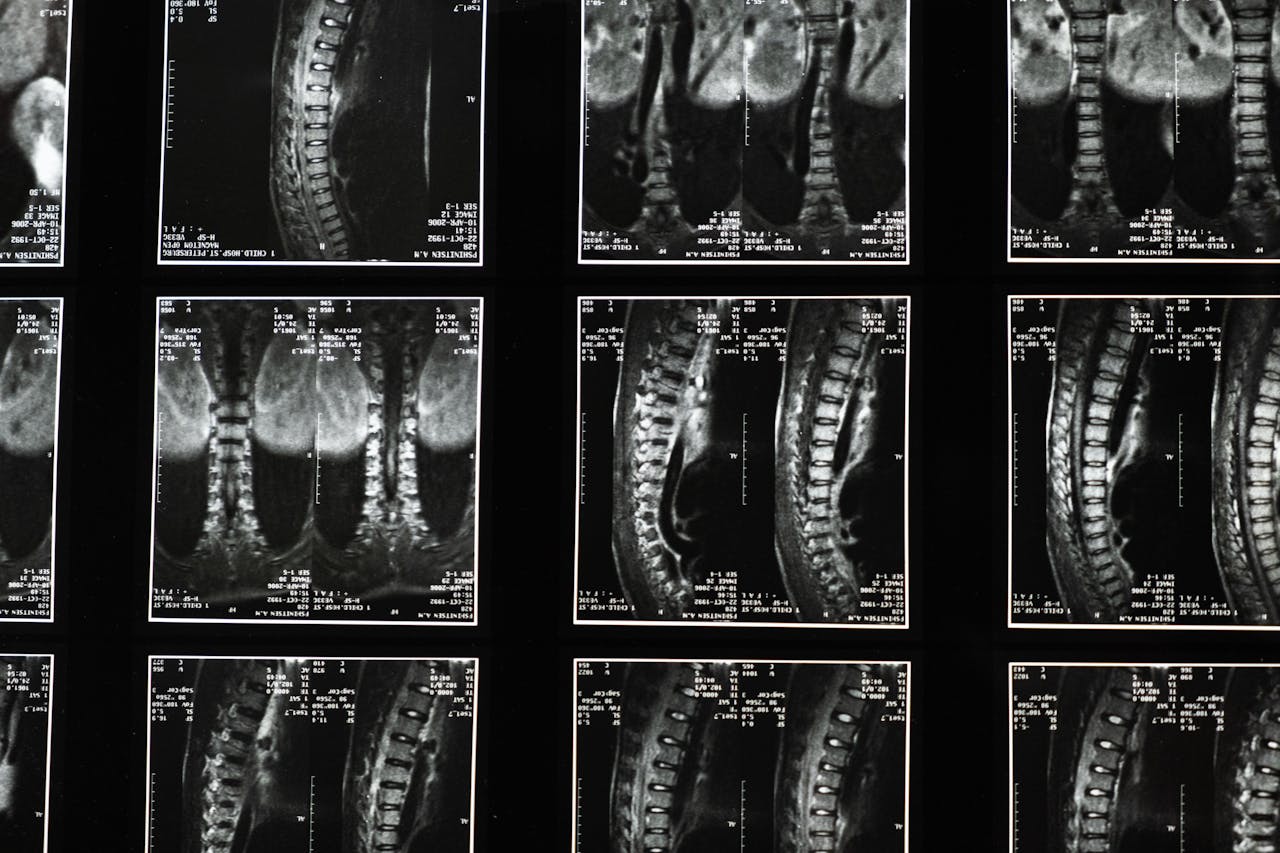

Back Pain Relief

Effective solutions for your back pain. Our experienced practitioners provide targeted treatments.